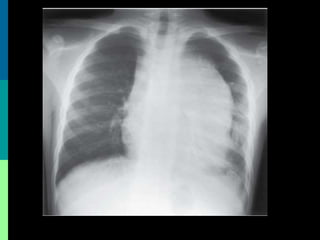

• Normochromic, Normocytic anaemia with

thrombocytopenia in most cases.

•The TWBCs count may be decreased, normal or

increased to 200 x 109/L or more.

•Blood film examination typically shows a variable

numbers of blast cells(>20% ).